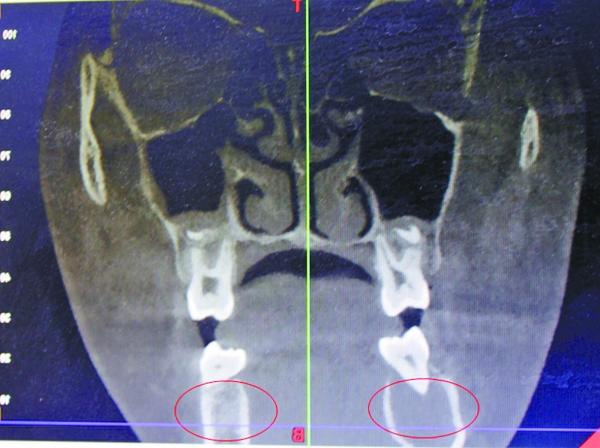

受血管瘤影响,右颌骨发生病变

据口腔医院医生王琨介绍,4月7日,在采取措施止血后,院方迅速为小玉进行了一系列检查,发现其患的是一种非常罕见的颌骨中央性血管瘤。“下牙槽里的动脉血管发生病变,长了若干细微的支血管,将她的颌骨破坏后发生出血。”

宋庆高博士说,受血管瘤病变影响,女孩的右颌骨,已经形成8×2.5厘米大小的腔窦,“相当于一个空洞。”从方便手术考虑,完全可能将她右侧颌骨去掉,但那样会形成面部缺陷,影响美观,而且右侧无法长牙。